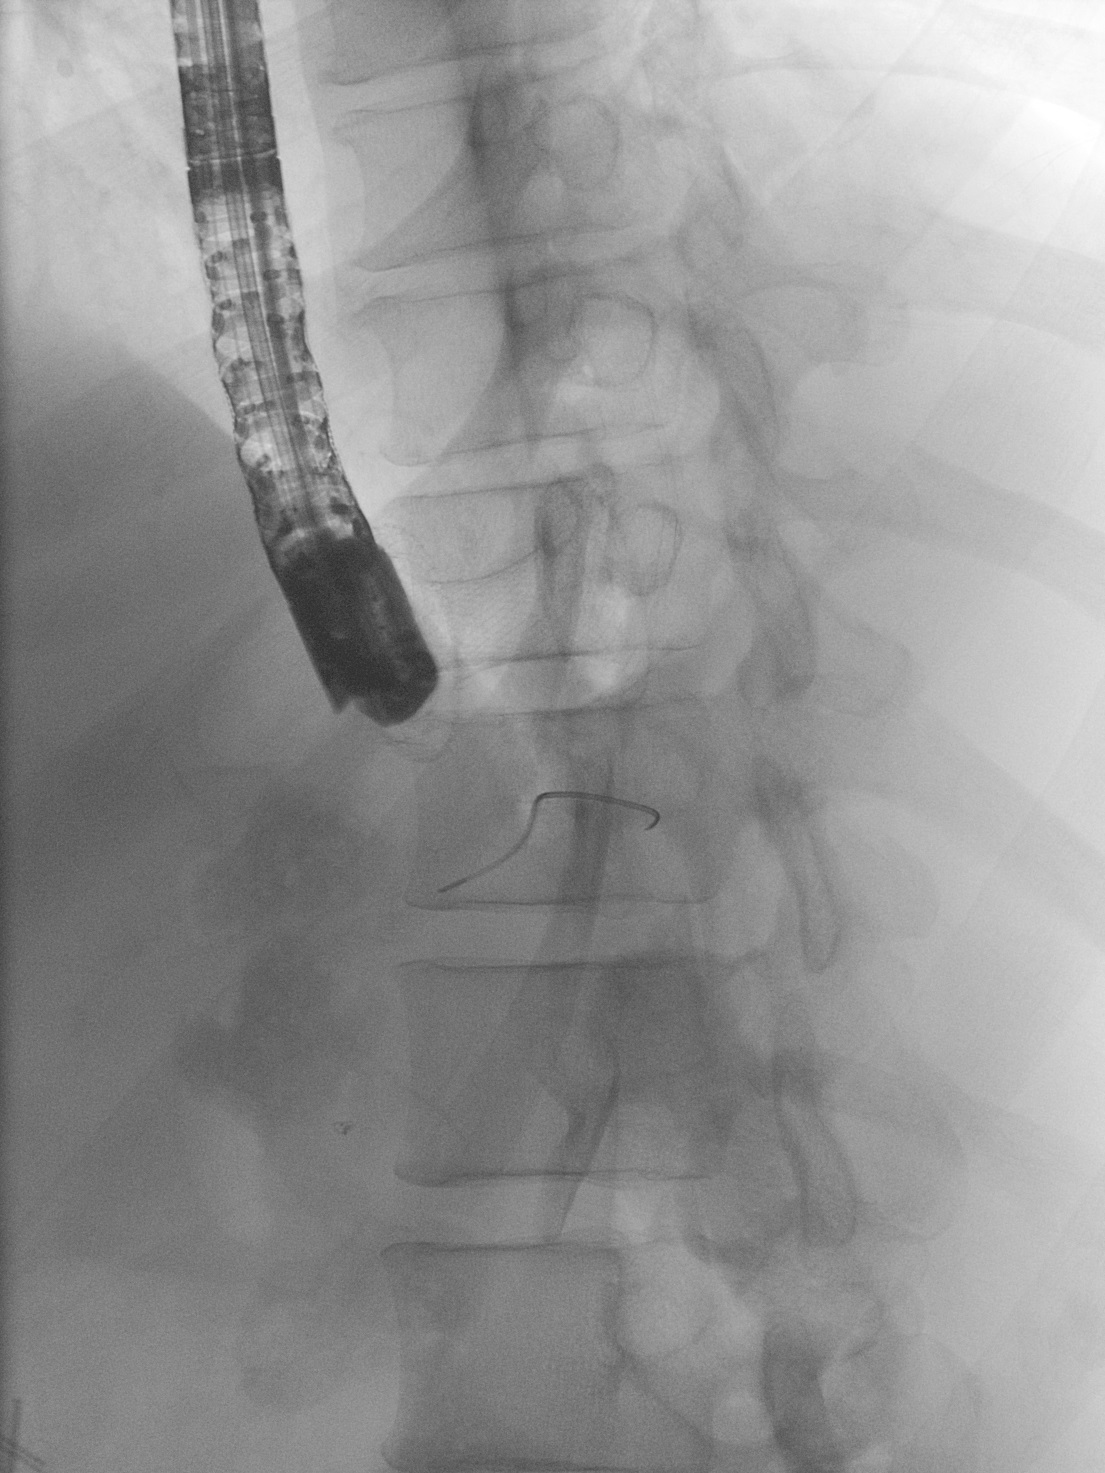

EDGE procedure: esophageal stent to the rescue (2.º Classificado - Vídeo)

Joel Ferreira-Silva, Filipe Vilas-Boas, Eduardo Rodrigues-Pinto, Pedro Pereira, Guilherme Macedo

Centro Hospitalar Universitário de São João

A 39-years-old woman with history of Roux-en-Y gastric bypass was referred to us due to new onset jaundice caused by a pancreatic head adenocarcinoma. Endoscopic ultrasound directed transGastric ERCP (EDGE) was pursued. A 20mm lumen-apposing metal stent (LAMS) was placed between gastric pouch and gastric remnant. Endoscopic retrograde cholangiopancreatography was performed 1 week later. However, LAMS position did not allow duodenoscope passage. A 23x125mm fully-covered metal stent was deployed in a trans-LAMS position, modifying LAMS positioning and allowing passage into gastric remnant. Subsequent biliary cannulation allowed biliary metal stent deployment. Esophageal stent was then removed and LAMS remained in situ.